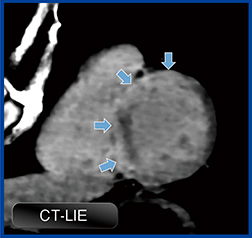

1.CT遅延造影(late iodine enhancement:LIE)

CT遅延造影は,造影平衡相における心電図同期撮影を行うだけのシンプルかつ実用的な手法である。MRIと比べてコントラスト分解能が劣るが,近年では,低管電圧撮影技術やdual energy撮影の仮想単色X線低エネルギー画像の活用によりコントラスト分解能が大きく向上し,実用化のレベルにある。冠動脈CTに遅延造影撮影を追加することで,付加的な情報を得ることができる(図3)。

図3 CT遅延造影:心サルコイドーシス

胸部不快感と不整脈の原因精査のため,心臓CTが施行された症例。冠動脈に有意狭窄はなかったが,CT遅延造影にて前壁から中隔の外層優位に広範なLIEを認めた。その後,心サルコイドーシスの診断に至った。